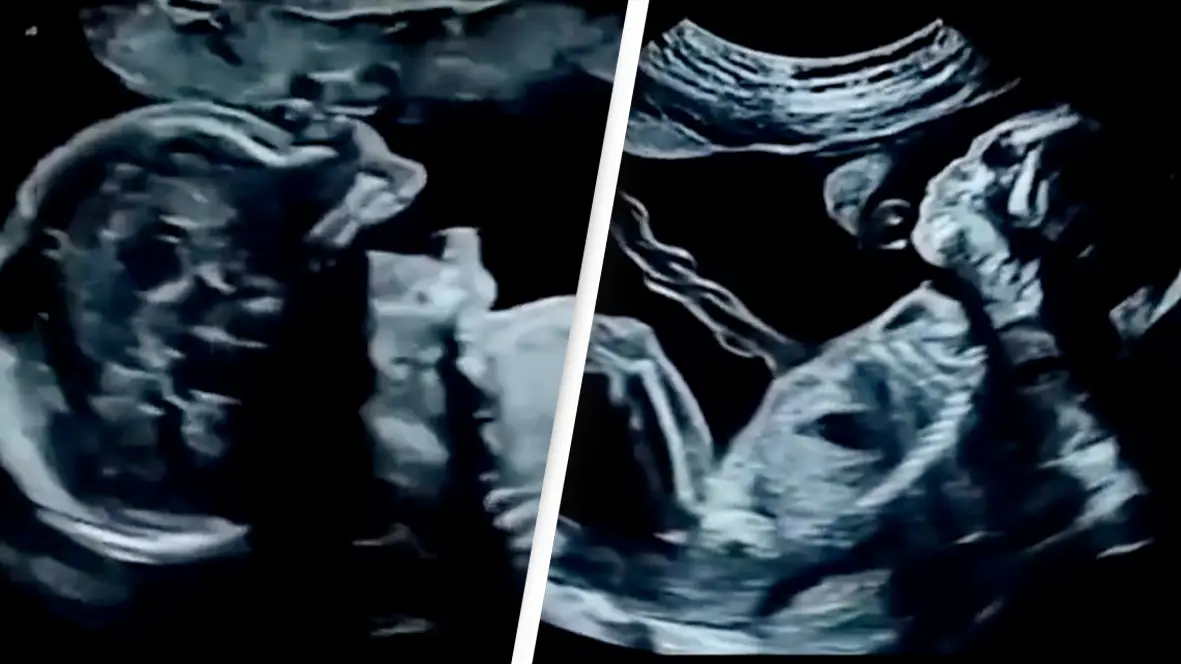

Craniopagus conjoined twins Minal and Mirha were born sharing blood vessels and brain tissue